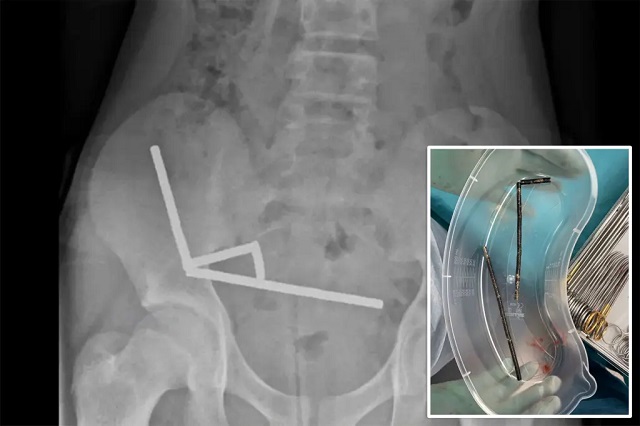

International Desk: पेट दर्द से परेशान 13 साल के एक लड़के ने डॉक्टरों के सामने चौंकाने वाला खुलासा किया कि उसने लगभग 200 छोटे नियोडिमियम चुंबक निगल लिए हैं। यह घटना न केवल बच्चों के स्वास्थ्य पर बल्कि ऑनलाइन बिक्री में उपलब्ध खतरनाक वस्तुओं पर गंभीर सवाल खड़े करती है। न्यूजीलैंड मेडिकल जर्नल में प्रकाशित केस रिपोर्ट के अनुसार, लड़के ने डॉक्टरों को बताया कि उसने 80-100 चुंबक निगले थे, लेकिन ऑपरेशन के दौरान लगभग 200 चुंबक निकाले गए। लड़के ने डॉक्टरों को बताया कि उसने लगभग चार-पाँच दिन पहले ये चुंबक निगले थे।

शुरुआती पेट दर्द के बाद हालत बिगड़ गई और अंततः उसे टौरंगा अस्पताल में भर्ती कराया गया।डॉक्टरों ने एक्स-रे और अन्य जांचों के बाद पाया कि उसके पेट और आंत में चार श्रृंखलाओं में चुंबक फंसे हुए थे। चुंबक एक-दूसरे को खींच रहे थे और आस-पास की आंतों की रक्त आपूर्ति बाधित कर रहे थे। इससे नेक्रोसिस के कई पैच बन गए, जिन्हें तुरंत सर्जरी के जरिए हटाना पड़ा। ऑपरेशन में चुंबक और क्षतिग्रस्त आंत के हिस्से निकाले गए। लड़के को आठ दिन अस्पताल में रहना पड़ा, लेकिन अब उसकी हालत स्थिर बताई जा रही है।डॉक्टरों ने चेतावनी दी कि छोटे उच्च शक्ति वाले चुंबक निगलने से आंत में छेद, हर्निया और लंबे समय तक पेट दर्द जैसी गंभीर जटिलताएं हो सकती हैं।